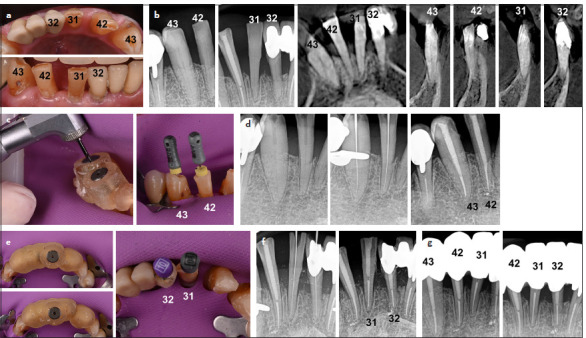

根管钙化是根管治疗的一大难题,可能导致治疗失败。困难在于进入、穿透和通过这些运河。本文报道了一系列的钙化根管成功治疗使用静态引导牙髓学。本文对11例钙化根管进行了静态引导根管治疗。样本包括四种牙齿类型,包括一个有两个管的前磨牙,使用两个模板(钻导)有效地管理。引导根管治疗是基于临床、放射学和锥束计算机断层扫描(CBCT)结果诊断的钙化根管的证据。采用高分辨率CBCT和口内扫描进行虚拟腔规划。CBCT和口内扫描叠加,虚拟滑套精确放置,以避免钻偏。制作并安装模板,低速钻孔引导入路,术中x线片监测。用k型锉平整运河,用Wave One Gold系统制备,2.5% NaOCl为灌溉剂。在所有情况下,虚拟规划的引导冠状和根管通道与3D打印模板相结合,可以通过封闭的牙髓空间进行根管定位,采用保守的进入方法,不会发生事故。这些病例表明,静态引导的牙髓治疗是一种安全准确的治疗方法,可以进入钙化管,减少工作时间,最大限度地减少牙齿结构的移除,降低医源性损伤的风险。(eej - 2024 - 07 - 106)。

Root canal calcification poses a substantial challenge in endodontic practice and may lead to treatment failure. The difficulty lies in accessing, penetrating, and negotiating these canals. This article reports on a series of calcified root canals successfully treated using static-guided endodontics. Eleven cases of calcified root canals were treated by the same endodontist using static-guided endodontics. The sample encompassed four tooth types including a premolar with two canals, effectively managed using two templates (drill guides). Guided endodontic treatment was based on evidence of calcified root canals diagnosed with clinical, radiographic, and cone beam computed tomography (CBCT) findings. A high-resolution CBCT and an intraoral scan were used for virtual cavity planning. The CBCT and intraoral scan were superimposed, and virtual sleeves were accurately placed to avoid drilling deviation. Templates were fabricated and fitted, and guided access was conducted with low-speed drilling, monitored with intraoperative radiographs. Canals were negotiated with K-files, and prepared with Wave One Gold system, using 2.5% NaOCl as irrigant. In all cases, virtually planned guided coronal and root canal access allied to the 3D printed templates allowed canal location through obliterated pulp spaces with a conservative access approach and without accidents. The cases demonstrated that static-guided endodontics is a safe accurate treatment approach to access calcified canals, reducing working time, minimizing removal of tooth structure, and decreasing the risk of iatrogenic damage. (EEJ-2024-07-106).